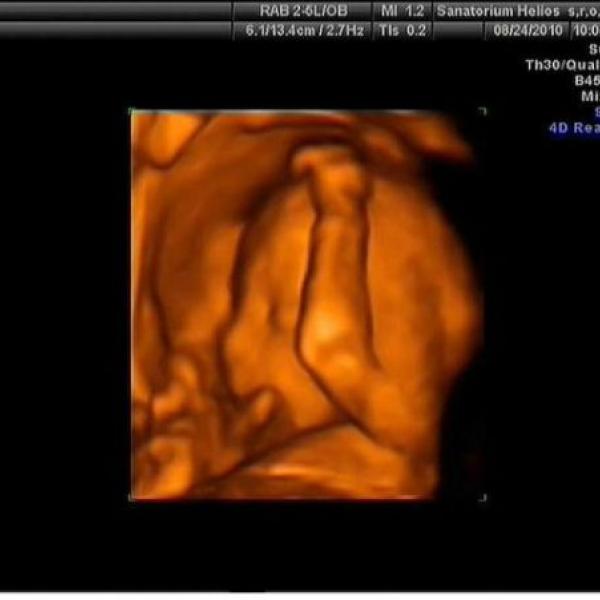

Ahoj spolutěhulinky :) tak jsem konečně taky vyfotila domeček našeho Tobíka :h: je to focené před týdnem v 30tt a už teď mi přijde, že mám pupík zase větší :00: Večer už mi vad